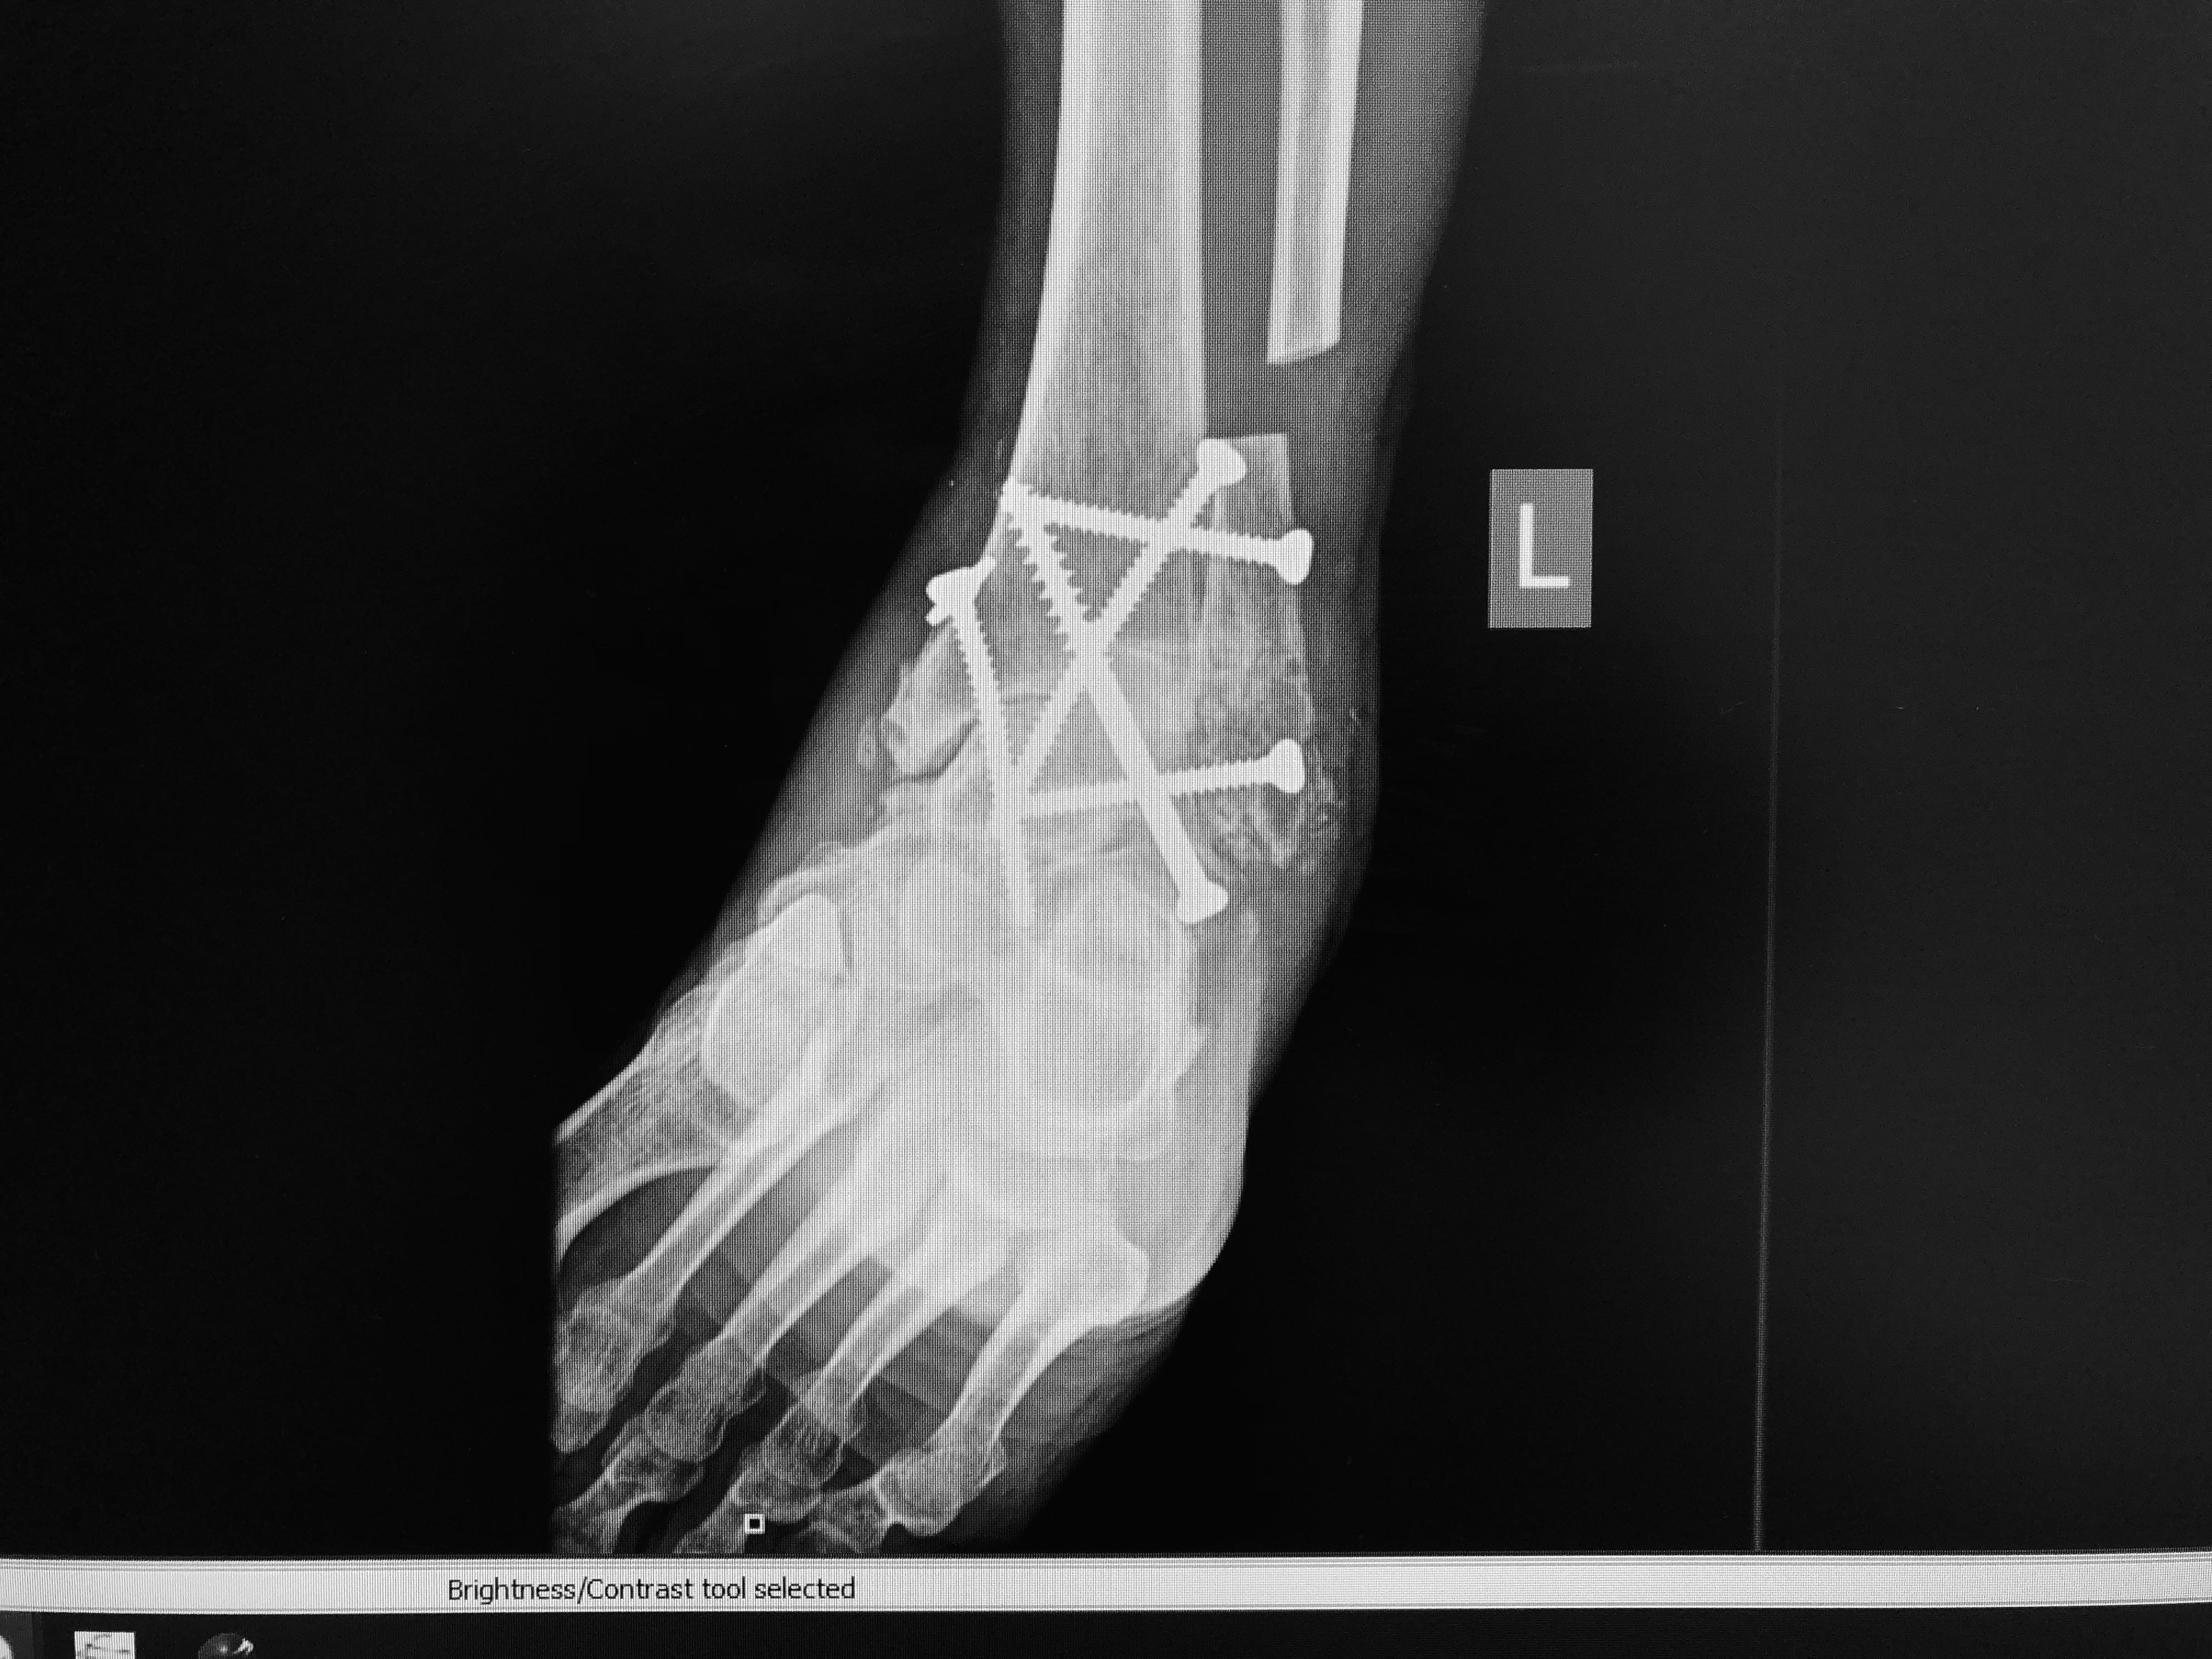

On the drive from Bozeman to Missoula I finally read the race email and realized that Mark could join me for a lap. The race allowed it and after years of pain, surgeries, and recovery, Mark’s body allowed it too. He hadn’t brought any running gear (and with a fused ankle he wouldn’t run regularly but for something special…). A cotton t-shirt and his regular sneakers would do. At the aid station at the bottom of the course, Mark asked around about borrowing some hiking poles. He met Jordan. Jordan had been a student in attendance at Mark’s presentation at Northern Michigan University the year prior. Jordan moved out here after. “You can borrow my poles,” he said. We never know where a chance encounter may lead. Someone might attend one of your talks and then hand over a set of hiking poles so you can go and run beside your Love for the very first time. Strangers become friends. They can help us change our history. Thank you.

I didn’t think I’d ever get the chance to run with Mark. I’d watched him with tears in his eyes, lean his weight onto a shopping cart, to alleviate the incredible pain he was in while grocery shopping for us before his surgeries. I never let myself hope we’d get to move together because that seemed too far to reach for, to try for. Just take away my Love’s pain. To ask for adventure as well felt like asking too much. But what happens when someone with an incredible internal well reaches in and asks for a little more? Small changes over time. Over time over time over time. Evolution.